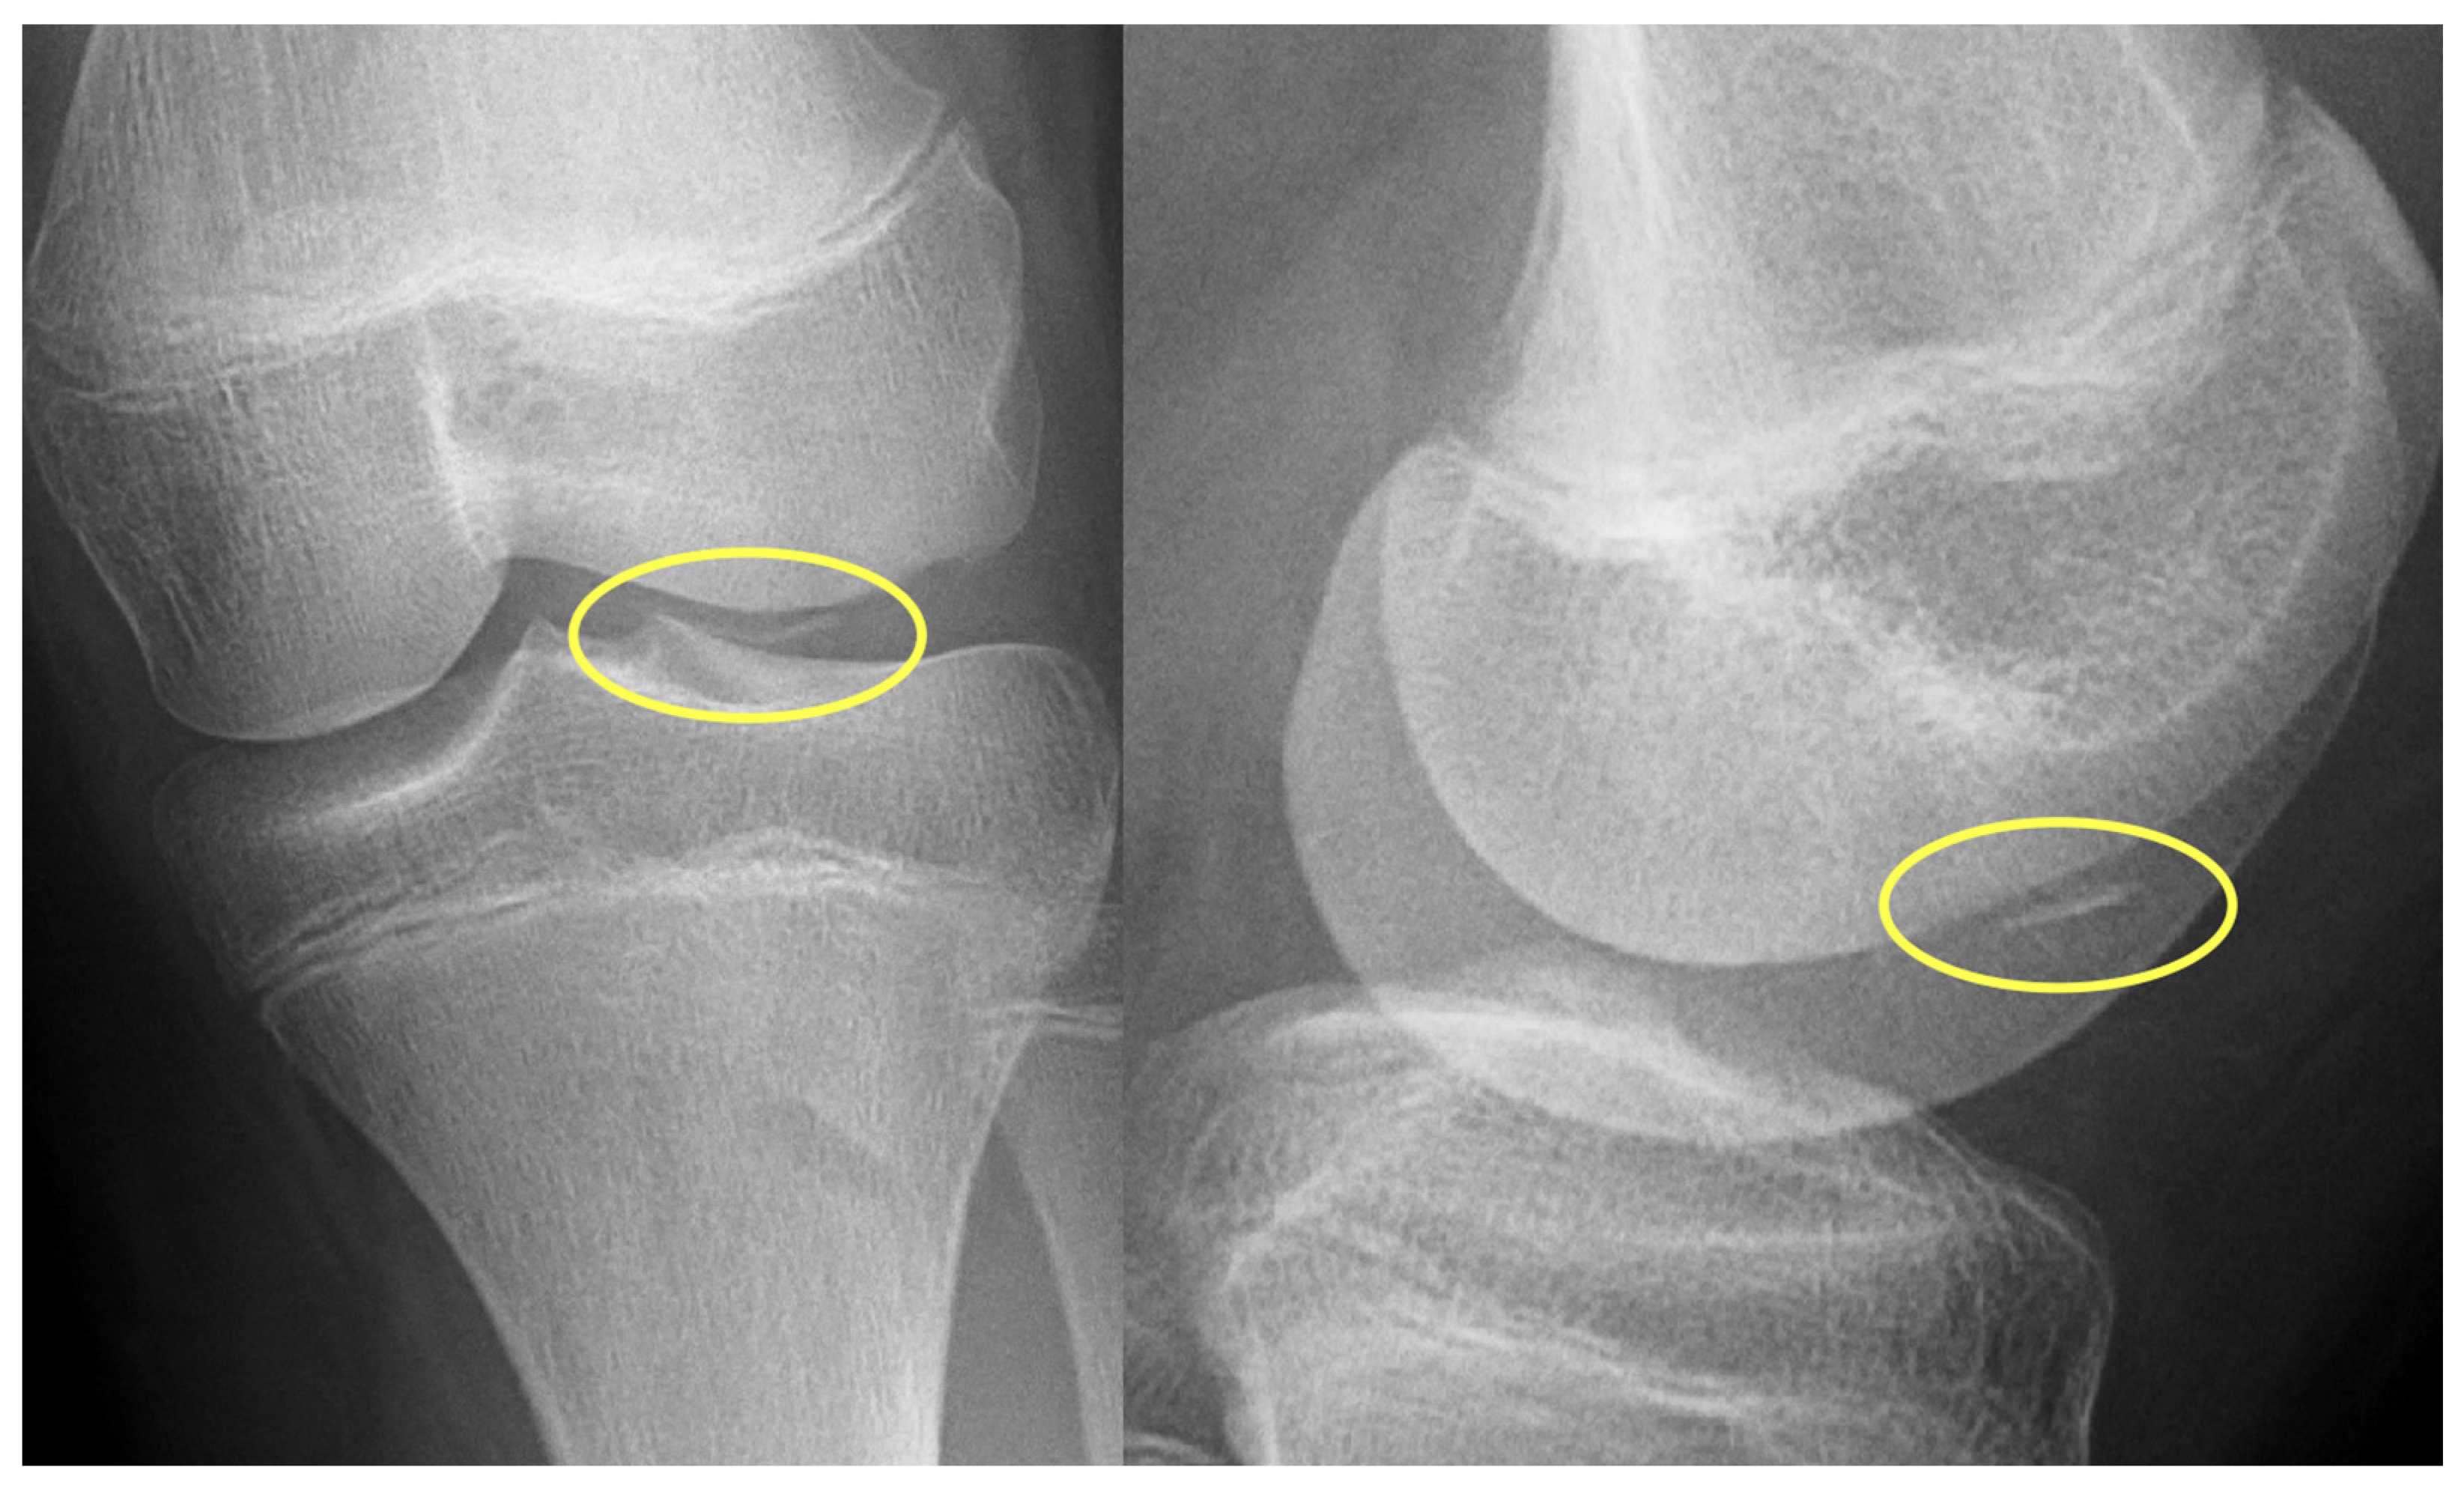

First patient: A nine-year-old girl injured her knee during a careless step, resulting in a sprain. The left knee was slightly swollen and the patient complained about pain, but other pathologies could not be identified with the physical examination. Therefore, an X-ray was requested. Results revealed an approximately 8 mm large broken piece of the femur’s lateral condyle, positioned at the border of the lateral recess (Figure 1).

Figure 1.

Preoperative X-ray showing the osteochondral fragment (yellow circle) of the lateral condyle of the femur.